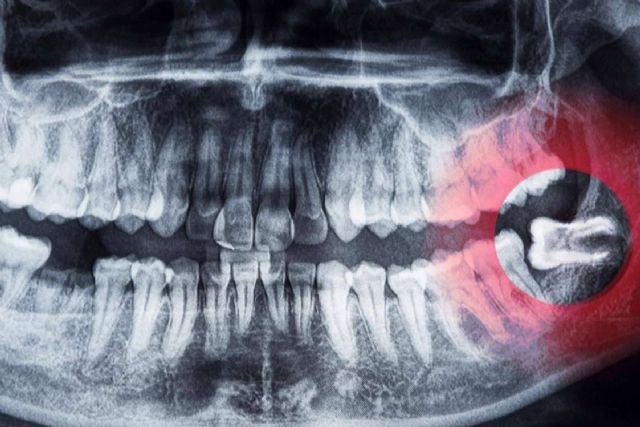

Las últimas muelas que suelen aparecer en la boca a una edad comprendida entre los 17 y los 25 años son las cordales o terceros molares.

En algunas personas, las cordales nunca llegan a brotar y, en otras, pueden causar problemas debido a su posición. En los casos de mayor gravedad, los especialistas recomiendan la extracción de los molares si existe algún cambio en la zona donde están esas muelas, por ejemplo: dolor, infección o quistes. Dicho procedimiento siempre debe ser realizado por un especialista en cirugía bucal y maxilofacial, ya que pueden presentarse complicaciones si el procedimiento no es correctamente realizado. Actualmente, existen clínicas de salud dental dedicadas a la extracción de cordales, como es el caso de Cibumaxi.

Los odontólogos también advierten que los terceros molares retenidos pueden causar graves problemas en la salud dental. Los dolores agudos, lesiones dentales y encías hinchadas son las consecuencias más frecuentes. Además, algunas personas pueden experimentar inflamación en la mandíbula, formación de quistes, tumoraciones, neuralgias y dificultad para abrir la boca.